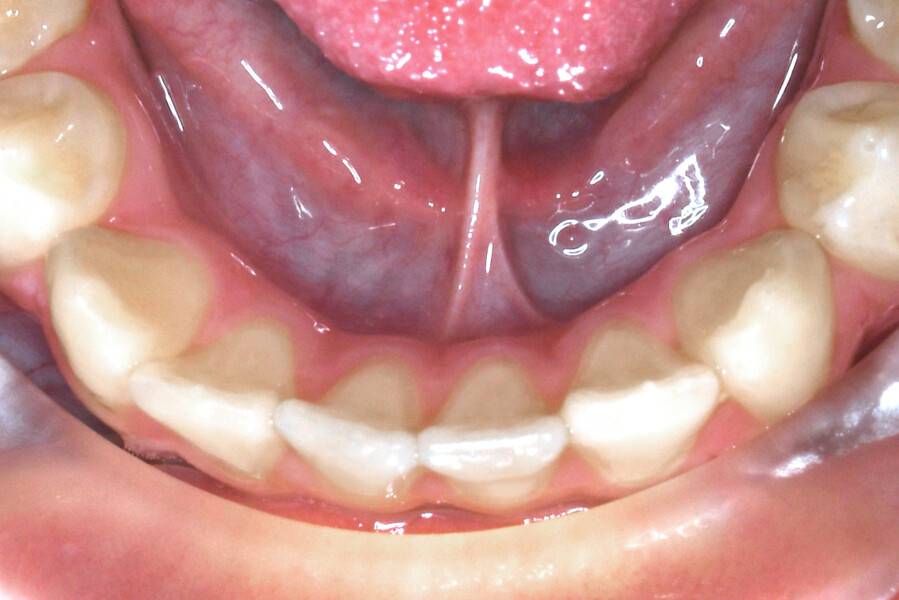

8 лет, девочка, жалобы на неправильный прикус и дефицит места зубам

Исправление прикуса

2,5 года

Выполнено лечение с помощью LM-активатора на ночь